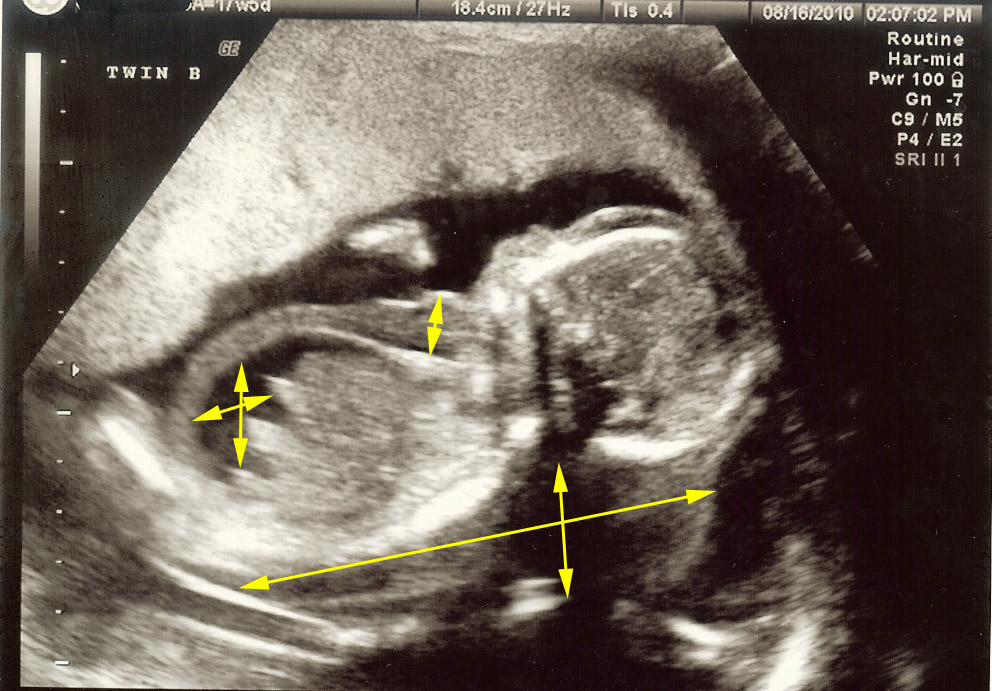

Cystic hygroma with hydrops fetalis Image

cystic hygroma with hydrops fetalis fetal ultrasound YouTube Hygroma Baby In Womb A cystic hygroma forms when the lymph vessels fail to form correctly during the first few weeks of pregnancy. It forms from pieces of material that carry fluid and white blood cells. A cystic hygroma is an uncommon finding that is sometimes seen during the routine early pregnancy scan. A cystic hygroma is a rare type of cyst that babies. Hygroma Baby In Womb.

Cystic hygroma with hydrops fetalis Image Hygroma Baby In Womb It forms from pieces of material that carry fluid and white blood cells. A cystic hygroma is a rare type of cyst that babies can get, usually in their head or neck, if their lymphatic system gets blocked. What is a cystic hygroma? It cannot be prevented as it occurs. If the hygroma appears during pregnancy, there is a. A. Hygroma Baby In Womb.